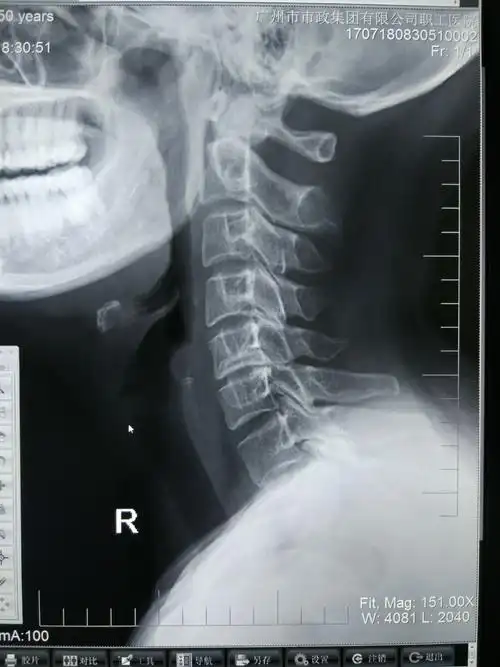

一例高位颈椎脱位并不全瘫患者的救治经过

市第一院骨二科成功救治一例高位颈椎骨折并完全脱位患者获得成功